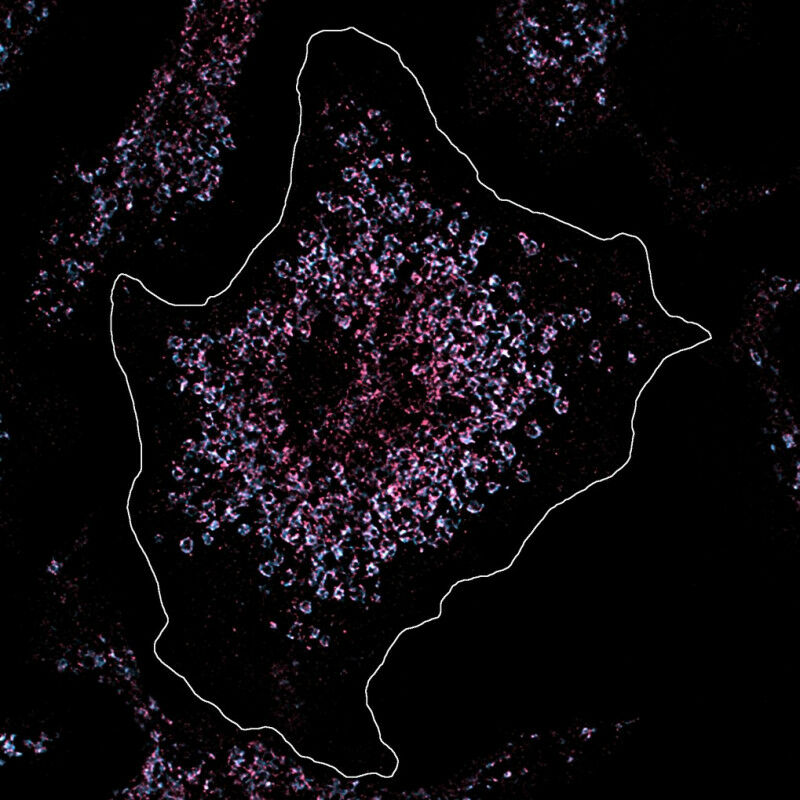

In dieser Zelle wurde Toll-like Rezeptor 7 pink angefärbt, um ihre Anzahl und Lage unter dem Mikroskop zu analysieren. Die Zelle ist gesund und die Anzahl der Toll-like Rezeptoren normal. Anders gestaltet es sich bei Immunzellen von Lupus-Patienten, die eine deutlich erhöhte Zahl von Rezeptoren aufweisen. Dadurch wird körpereigenes Erbgut erkannt und die chronischen Entzündungen des Lupus ausgelöst. © MPI f. Infektionsbiologie/ Fenja Blank

Eine einzelne Genmutation kann eine Form der Autoimmunerkrankung Lupus hervorrufen. In dieser Zelle wurde Toll-like Rezeptor 7 pink angefärbt, um ihre Anzahl und Lage unter dem Mikroskop zu analysieren. Die Zelle ist gesund und die Anzahl der Toll-like Rezeptoren normal. Anders gestaltet es sich bei Immunzellen von Lupus-Patienten, die eine deutlich erhöhte Zahl von Rezeptoren aufweisen. Dadurch wird körpereigenes Erbgut erkannt und die chronischen Entzündungen des Lupus ausgelöst. MPI f. Infektionsbiologie/ Fenja Blank - Manchmal genügt eine einzige Veränderung in unserem Erbgut, um uns krank zu machen. So auch bei der Autoimmunkrankheit Lupus, die durch starke Entzündungen im ganzen Körper das Leben der Betroffenen entscheidend beeinträchtigt. Forschende des Max-Planck-Instituts für Infektionsbiologie in Berlin haben einen Mechanismus entdeckt, der Lupus bei Kindern auslösen kann.